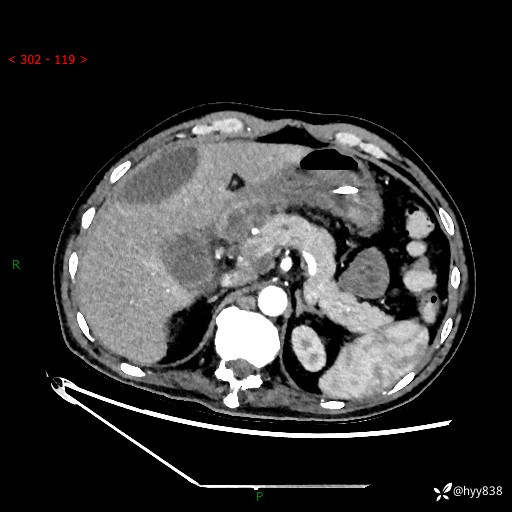

腹部CT平扫

增强